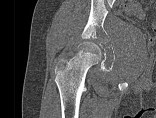

- 单项选择题如图所示,患儿的最可能的诊断是 ( )

A、骨髓炎

B、尤文肉瘤

C、骨肉瘤

D、软骨肉瘤

E、以上都不是